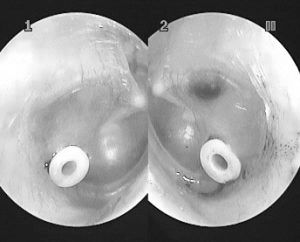

Важкі форми отиту нерідко передбачають втручання хірурга і трубку для дренажу, що вставляється в барабанну перетинку для відновлення відтоку скупчилися виділень. Трубку після лікування витягують оперативним шляхом, причому медики вважають побоювання батьків з приводу подібного втручання безпідставними, так як процедуру проводять під місцевою анестезією, а больові відчуття відсутні. Ефективність такого методу підтверджується швидким одужанням дитини протягом одного тижня.